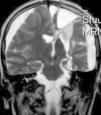

En cuanto a las medidas terapéuticas, inicialmente recibió tratamiento con carbamacepina, con empeoramiento del cuadro (aparición de mioclonías frecuentes en extremidades derechas). Se interrumpió el tratamiento y se instauraron clonazepam y clobazam, con mejoría a corto plazo. En los meses siguientes presentó aumento de mioclonías en los miembros derechos, pérdida de fuerza mantenida en los mismos y aparición de algún episodio de crisis parciales y alguna convulsión tónico-clónica generalizada. Ante el empeoramiento, se añadieron al tratamiento ácido valproico, corticoides y recibió 4 ciclos de inmunoglobulinas. No se volvieron a registrar convulsiones tónico-clónicas, pero se incrementó la frecuencia de crisis parciales y mioclonías. La degeneración motora y cognitiva también progresó, siendo incapaz de pronunciar muchas palabras, persistiendo paresia del miembro superior derecho y dificultades para la deambulación. Dado el fracaso del tratamiento médico, se decide remitir al mismo hospital de referencia para realización de tratamiento quirúrgico paliativo. A los 8 años y 8 meses de edad se le practica una hemisferectomía izquierda por vía frontal (figs. 3 y 4). En el acto quirúrgico se obtuvo una biopsia cerebral con inflamación perivascular, gliosis y degeneración neuronal compatible con encefalitis de Rasmussen.